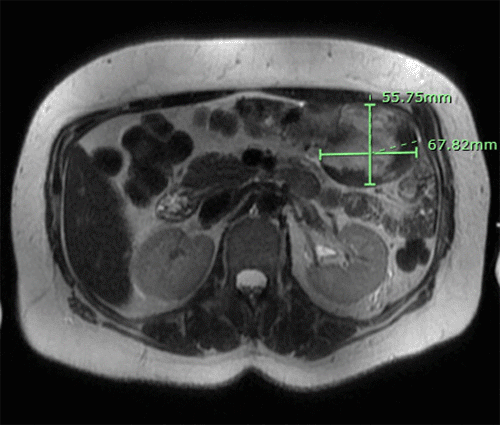

Histopathological examination revealed a subserosal fibromatosis extending into the small bowel wall without mucosal invasion (Figure 5A: H&E, x50). Higher magnification (Figure 5B: H&E, x400) showed spindle cell proliferation with somewhat ill-defined borders, comprised of uniform cells with plump ovoid nuclei and ample eosinophilic cytoplasm. The stroma was collagenous, focally edematous, and contained thin-walled small vessels scattered throughout the lesion. Additionally, some areas showed hyalinized, keloid-like changes. Resection margins were negative.

Figure 5. Hematoxylin and Eosin (H&E) Stains (50x and 400x, respectively). Published with Permission

B Proliferation of spindle-shaped cells featuring elongated, slender, and uniformly shaped nuclei with pale cytoplasm set within a collagenous stroma